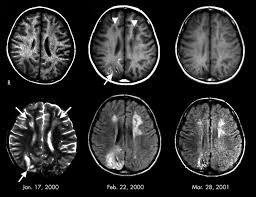

Guillain Barre Syndrome Mri / Figure 6 From Spinal Mri Findings Of Guillain Barre Syndrome Semantic Scholar - Typically, both sides of the body are involved, and the initial symptoms are changes in sensation or pain often in the back along with muscle weakness, beginning in the feet and hands, often spreading to the arms and upper body.. However, it can reveal nerve root enhancement and may be an effective diagnostic adjunct. Moreover, gbs is also associated with any vaccination. Its signs and symptoms are similar to those of other neurological disorders and may vary from person to person. Cerebral magnetic resonance imaging showed lesions in both frontal and right occipital lobes. Fisher syndrome, a clinical variant of guillain­ barre syndrome characterized by ataxia, are­ flexia, and ophthalmoplegia, brain stem lesions have been described with cranial mr.imaging (8).

Cerebral magnetic resonance imaging showed lesions in both frontal and right occipital lobes. Mri is sensitive, but nonspecific, for diagnosis. During a course of intravenous immunoglobulin therapy, she had headache with meningism. The most common result is a weakness and numbness that starts at the tips of the fingers and toes and spreads inward toward the body. Mr imaging findings in eight patients (three male, five female; 1 article features images from this case 14 public playlist includes this case Although no abnormalities were observed on brain and spinal magnetic resonance imaging and electroencephalography, peripheral nerve conduction velocity tests failed to evoke motor and sensory nerve action potentials. Typically, both sides of the body are involved, and the initial symptoms are changes in sensation or pain often in the back along with muscle weakness, beginning in the feet and hands, often spreading to the arms and upper body.